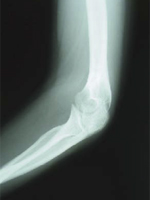

第24診(固定後61日目):レントゲン撮影。骨折部治癒(図8,9)。

図9 61日目X線 側面像 |